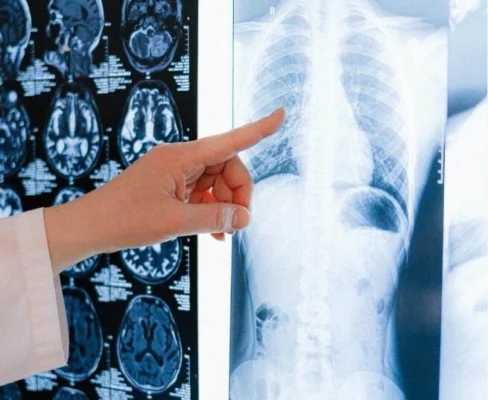

Methods And Technologies of Accurate Scoliosis Detection

Scoliosis is characterized by a three-dimensional distortion of the spine, involving a lateral curvature exceeding [...]